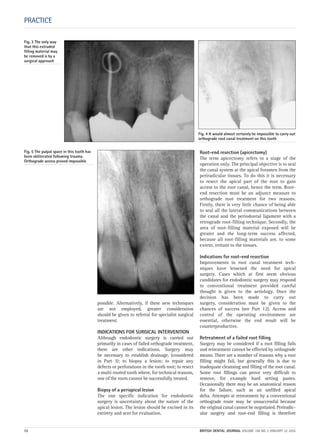

Difficulty with local analgesia is a common

problem with an acutely inflamed pulp. In

addition to standard techniques, supplemen-

tary analgesia can be obtained with the fol-

lowing:

1 Additional infiltration anaesthesia, such as

long-buccal, lingual and palatal.

2 Intraligamental (intra-osseous) injection.

3 True intra-osseous injection.

4 Intrapulpal analgesia.

5 Inhalational sedation with local analgesia.